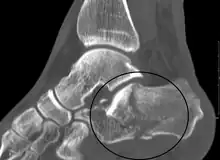

Conventional radiography is usually the initial assessment tool when a calcaneal fracture is suspected. Recommended x-ray views are (a) axial, (b) anteroposterior, (c) oblique and (d) views with dorsiflexion and internal rotation of the foot. However, conventional radiography is limited for visualization of calcaneal anatomy, especially at the subtalar joint. A CT scan is currently the imaging study of choice for evaluating calcaneal injury and has substituted conventional radiography in the classification of calcaneal fractures.[13] Axial and coronal views are obtained for proper visualization of the calcaneus, subtalar, calcaneocuboid and talonavicular joints.

.jpg)

Calcaneal fractures are categorized as intra-articular or extra-articular on the basis of subtalar joint involvement. Intra-articular fractures are more common and involve the posterior talar articular facet of the calcaneus. The Sanders classification groups these fractures into four types based on the location of the fracture at the posterior articular surface. Extra-articular fractures are less common and may be located anywhere outside the subtalar joint.[13] Extra-articular fractures are categorized depending on whether the involvement of the calcaneus is anterior (Type A), middle (Type B) or posterior (Type C).[15]

The Angle of Gissane, or "Critical Angle", is the angle formed by the downward and upward slopes of the calcaneal superior surface. On a lateral radiograph, an angle of Gissane > 130° suggests fracture of the posterior subtalar joint surface. Böhler's angle, or the "Tuber Angle", is another normal anatomic landmark seen in lateral radiographs. It is formed by the intersection of 1) a line from the highest point of the posterior articular facet to the highest point of the posterior tuberosity, and 2) a line from the former to the highest point on the anterior articular facet. Böhler's angle is normally 25° to 40°.[14] It is named after Austrian physician Lorenz Böhler.[16] A decreased angle is indicative of a calcaneal fracture.